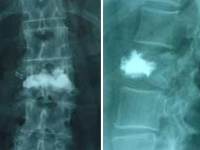

![]() Cifoplastia con balón. Fractura aplastamiento DX y DXI |